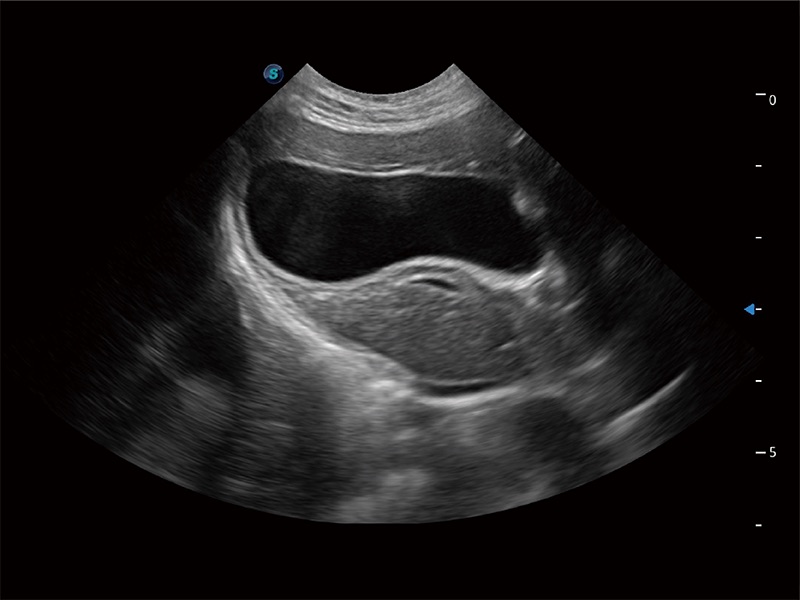

• Auto Bladder 膀胱自动测量

一键自动识别膀胱壁及自动测量膀胱容积,不受膀胱形状和大小的限制,帮助医生快速精准获得测量的数据。

(犬)胎儿四腔心